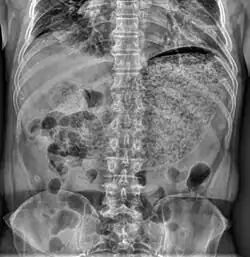

Gastropareza (łac. gastroparesis, ang. weak stomach) – następstwo neuropatii autonomicznej polegające na zaburzeniu (spowolnieniu) opróżniania żołądka. Występuje u 4% populacji.